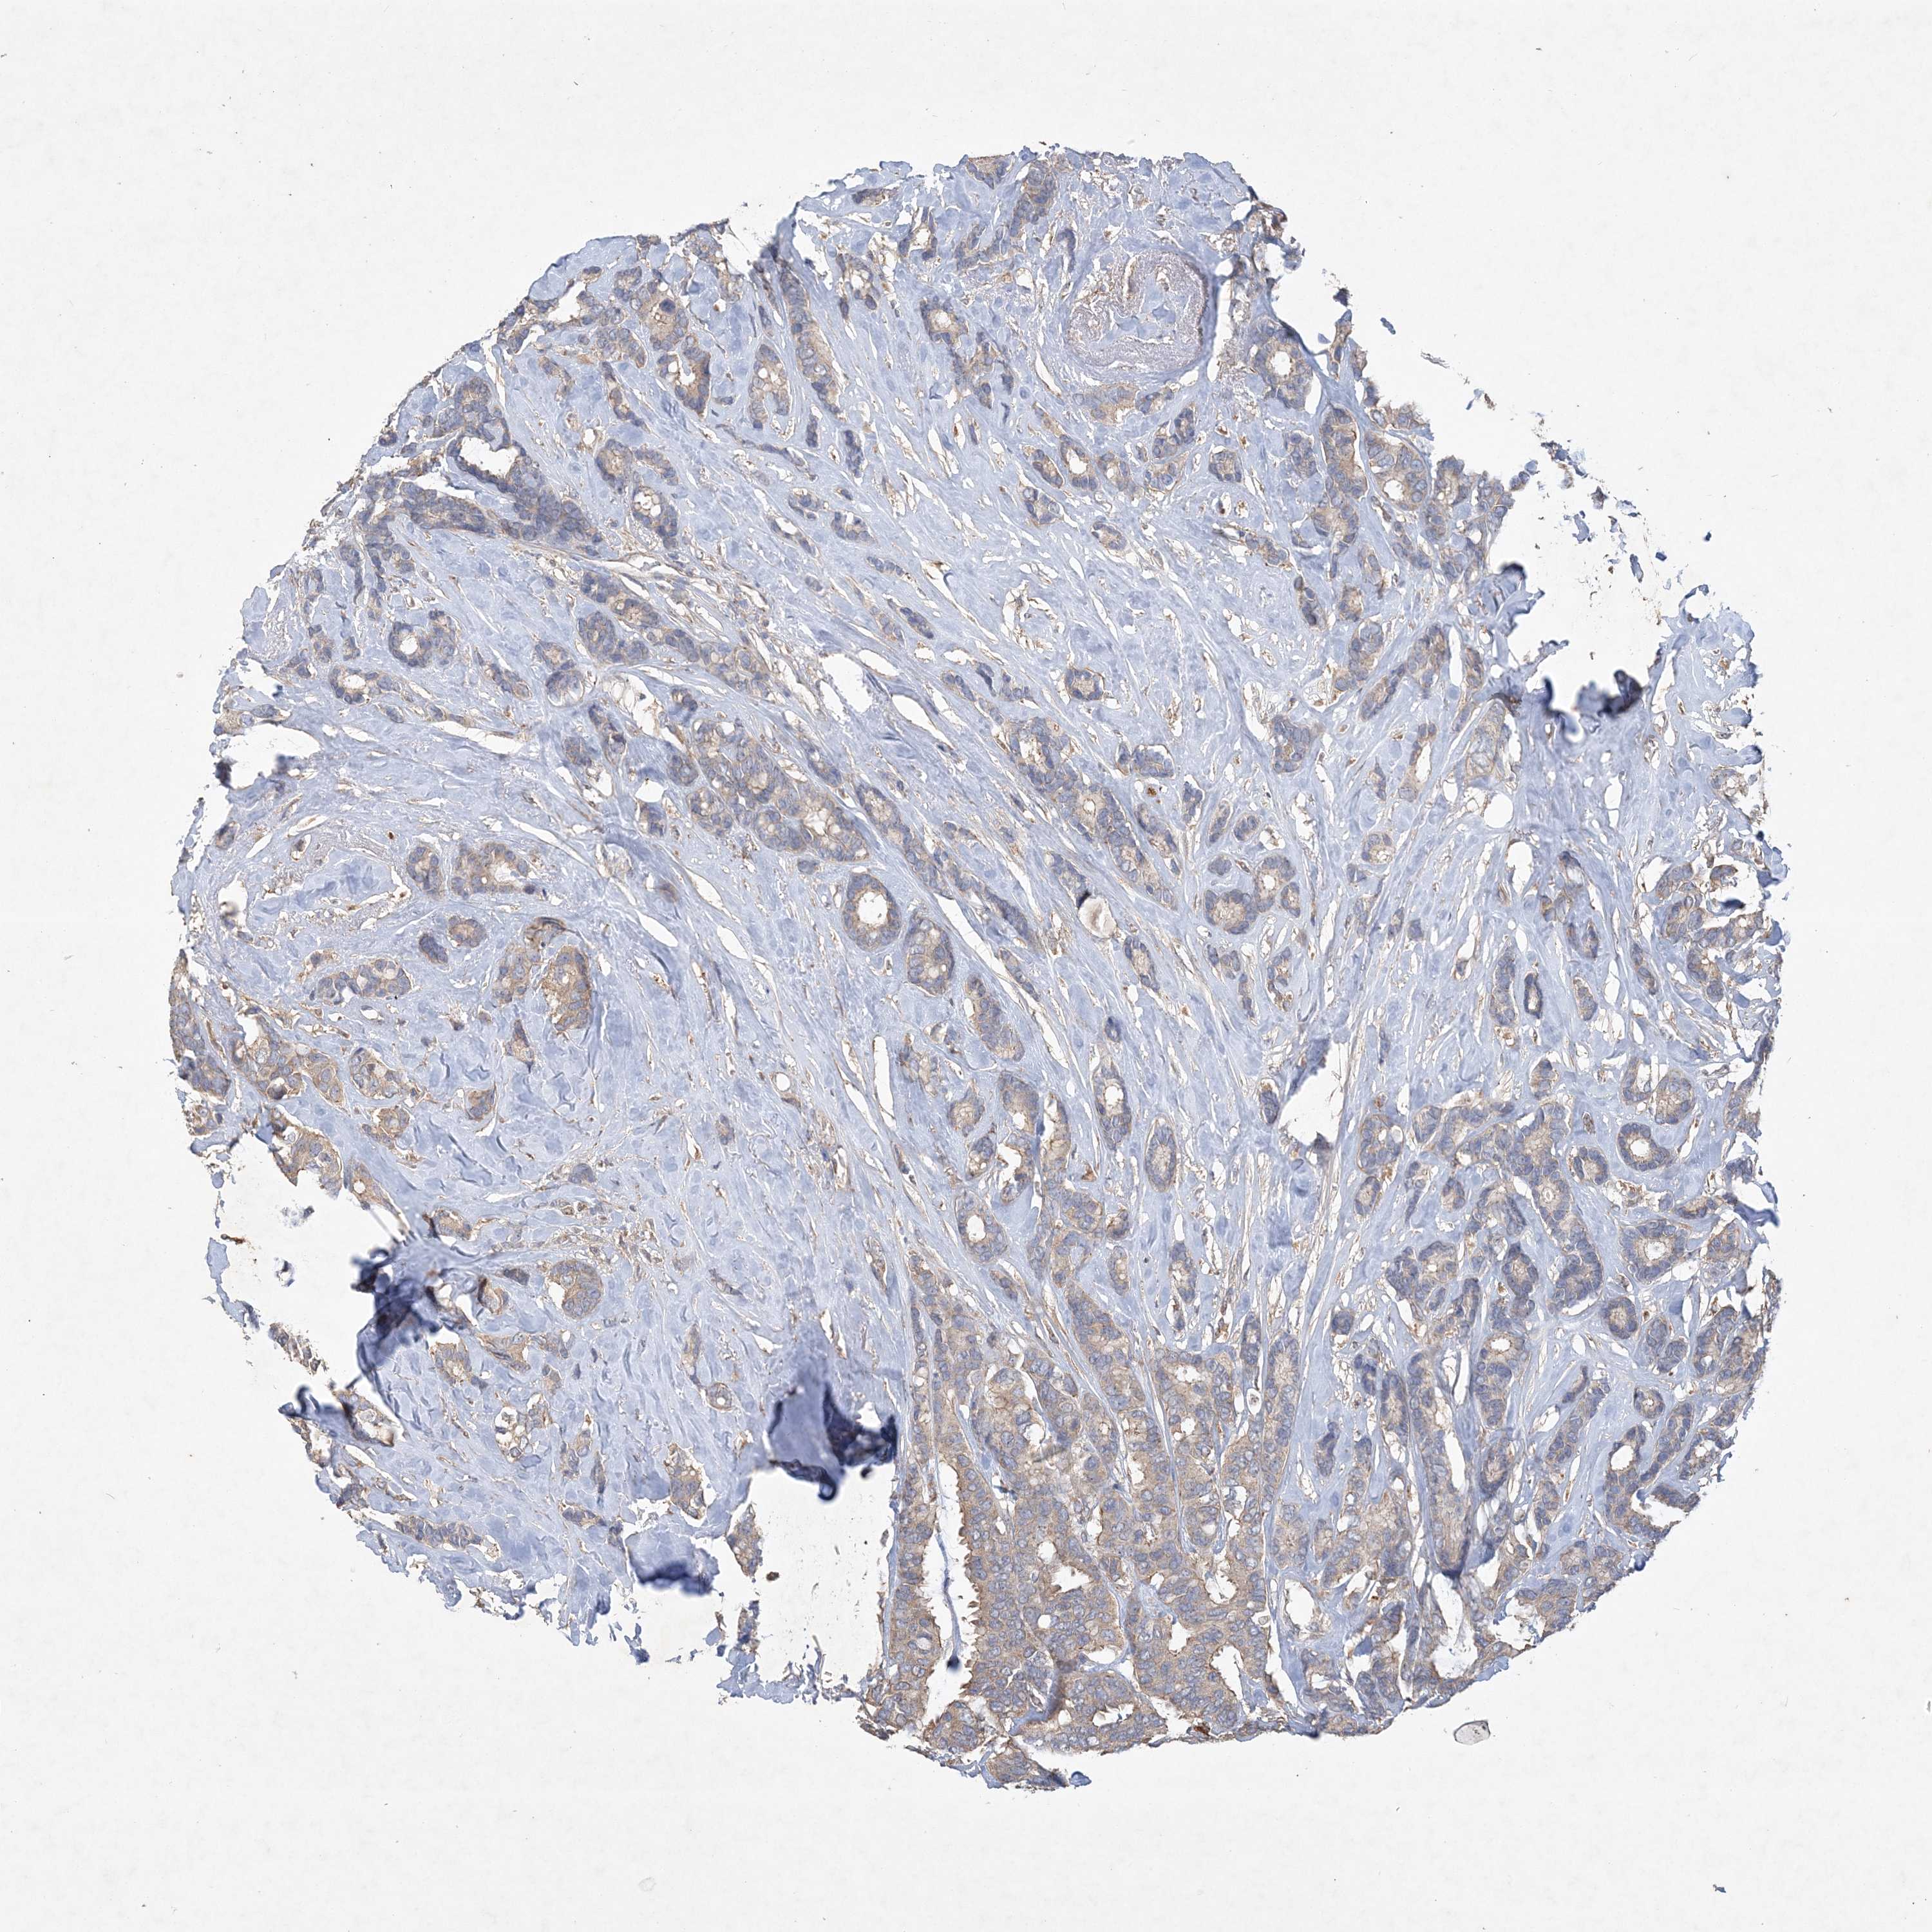

CANCER BREAST CANCER Show tissue menu

BRCA TCGA BRCA VALIDATION PROTEIN EXPRESSION